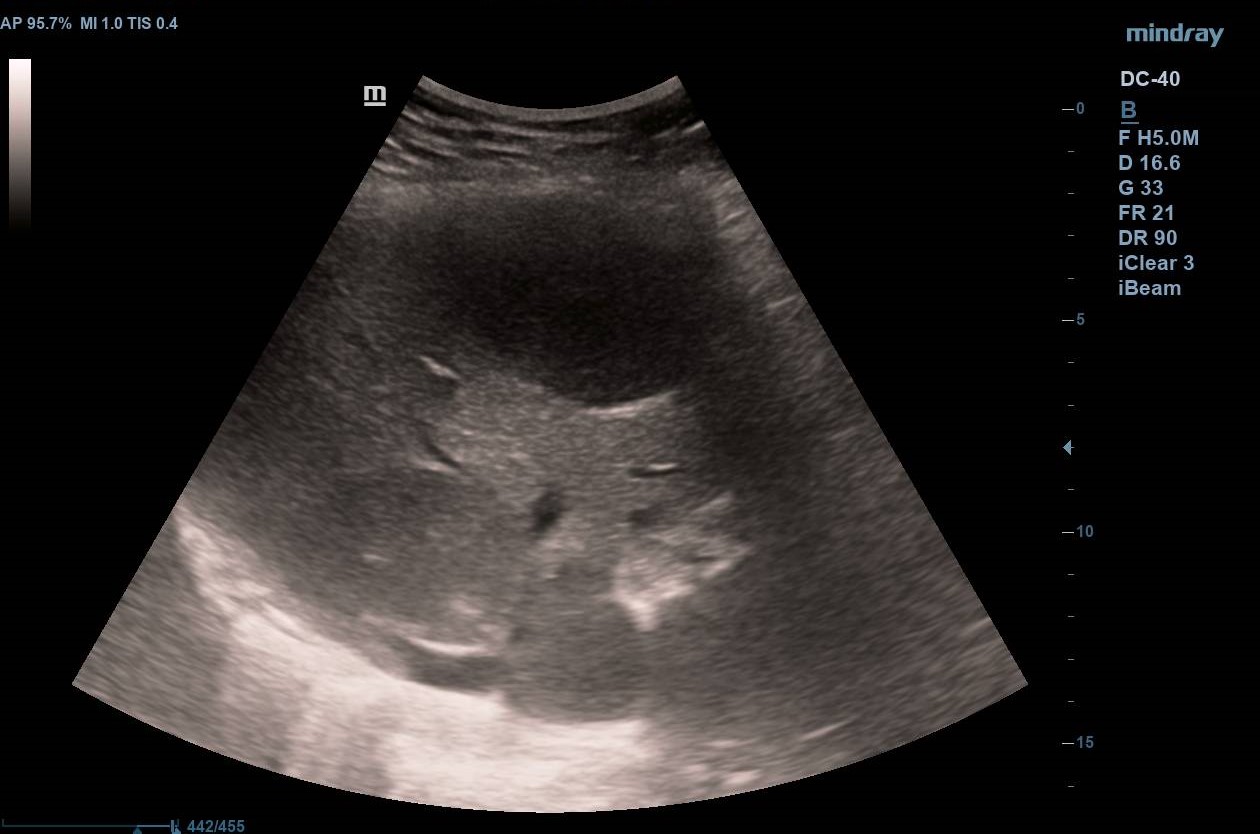

Ecografía inicial con ecógrafo portátil con múltiples LOES hepáticas hipoecogénicas de 5-6 cm de diámetro, alguna con centro hiperecogénico (figuras 1 y 2), que se confirman con ecógrafo de consola (figuras 3 y 4) con flujo Doppler aumentado respecto al resto de parénquima (hay vídeos).